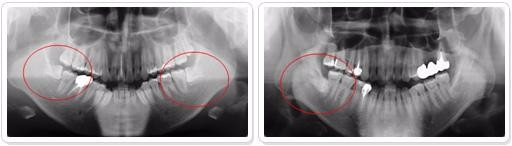

4、阻生智齿必须拔除。智齿是人类进化中逐渐退化的牙齿,临床建议智齿可以拔除,当然如果智齿位置合适有对颌牙,可以选择拔除。但是想阻生智齿必须拔除,一来阻生智齿容易引起牙齿炎症给自己带来疼痛感,二阻生智齿在生长的过程中可能会严重影响邻牙的健康,三阻生智齿如果迫近血管,在生长过程可能会出现危险。